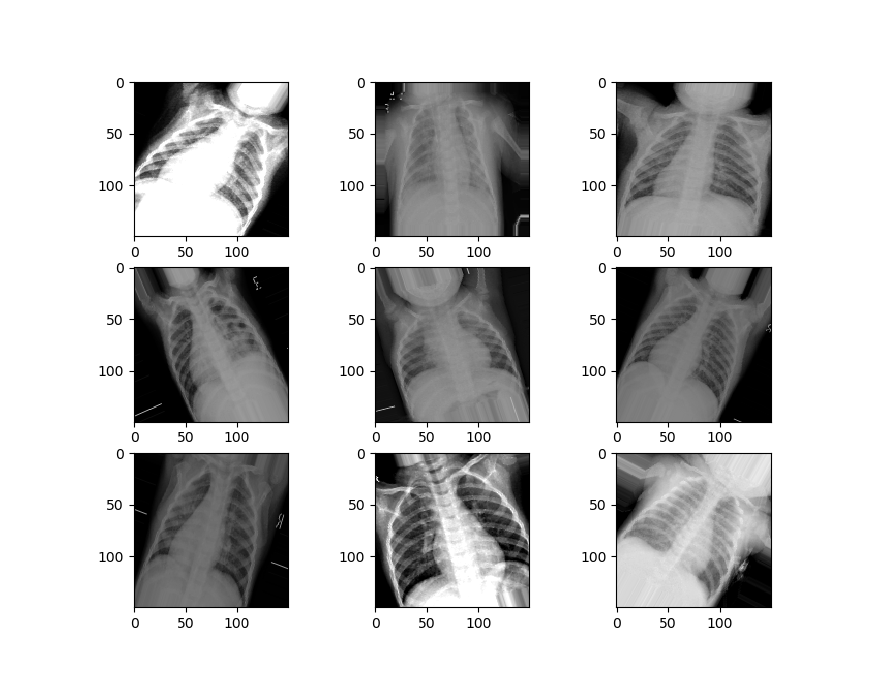

Now we’ll visualize the second set of data.

We can see that our second set of data is a little different from the first set. It’s zoomed in, rotated randomly, has image artifacts and more, to simulate the kinds of damages that might happen to an image in the real world.